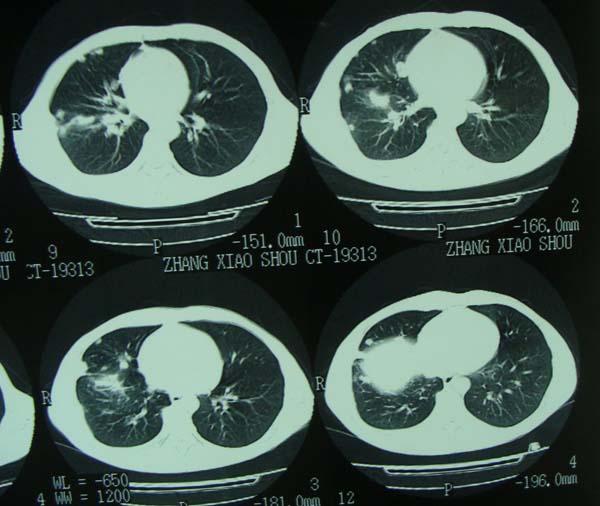

标题: CT15132:男,26岁。建筑混凝土工人。发热。咳。 [打印本页]

标题: CT15132:男,26岁。建筑混凝土工人。发热。咳。

右肺继发型肺结核,右侧胸腔积液、胸膜肥厚粘连。

右肺继发型肺结核,右侧胸腔积液。

年轻男性,右肺多形性病灶伴右侧胸腔积液,考虑结核